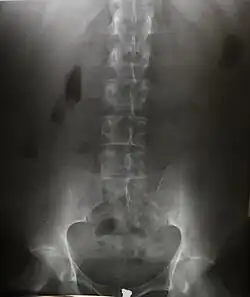

Radiography is an imaging technique using X-rays, gamma rays, or similar ionizing radiation and non-ionizing radiation to view the internal form of an object. Applications of radiography include medical ("diagnostic" radiography and "therapeutic radiography") and industrial radiography. Similar techniques are used in airport security, (where "body scanners" generally use backscatter X-ray). To create an image in conventional radiography, a beam of X-rays is produced by an X-ray generator and it is projected towards the object. A certain amount of the X-rays or other radiation are absorbed by the object, dependent on the object's density and structural composition. The X-rays that pass through the object are captured behind the object by a detector (either photographic film or a digital detector). The generation of flat two-dimensional images by this technique is called projectional radiography. In computed tomography (CT scanning), an X-ray source and its associated detectors rotate around the subject, which itself moves through the conical X-ray beam produced. Any given point within the subject is crossed from many directions by many different beams at different times. Information regarding the attenuation of these beams is collated and subjected to computation to generate two-dimensional images on three planes (axial, coronal, and sagittal) which can be further processed to produce a three-dimensional image.

Since the body is made up of various substances with differing densities, ionising and non-ionising radiation can be used to reveal the internal structure of the body on an image receptor by highlighting these differences using attenuation, or in the case of ionising radiation, the absorption of X-ray photons by the denser substances (like calcium-rich bones). The discipline involving the study of anatomy through the use of radiographic images is known as radiographic anatomy. Medical radiography acquisition is generally carried out by radiographers, while image analysis is generally done by radiologists. Some radiographers also specialise in image interpretation. Medical radiography includes a range of modalities producing many different types of image, each of which has a different clinical application.

Projectional radiography

The creation of images by exposing an object to X-rays or other high-energy forms of electromagnetic radiation and capturing the resulting remnant beam (or "shadow") as a latent image is known as "projection radiography". The "shadow" may be converted to light using a fluorescent screen, which is then captured on photographic film, it may be captured by a phosphor screen to be "read" later by a laser (CR), or it may directly activate a matrix of solid-state detectors (DR—similar to a very large version of a CCD in a digital camera). Bone and some organs (such as lungs) especially lend themselves to projection radiography. It is a relatively low-cost investigation with a high diagnostic yield. The difference between soft and hard body parts stems mostly from the fact that carbon has a very low X-ray cross section compared to calcium.